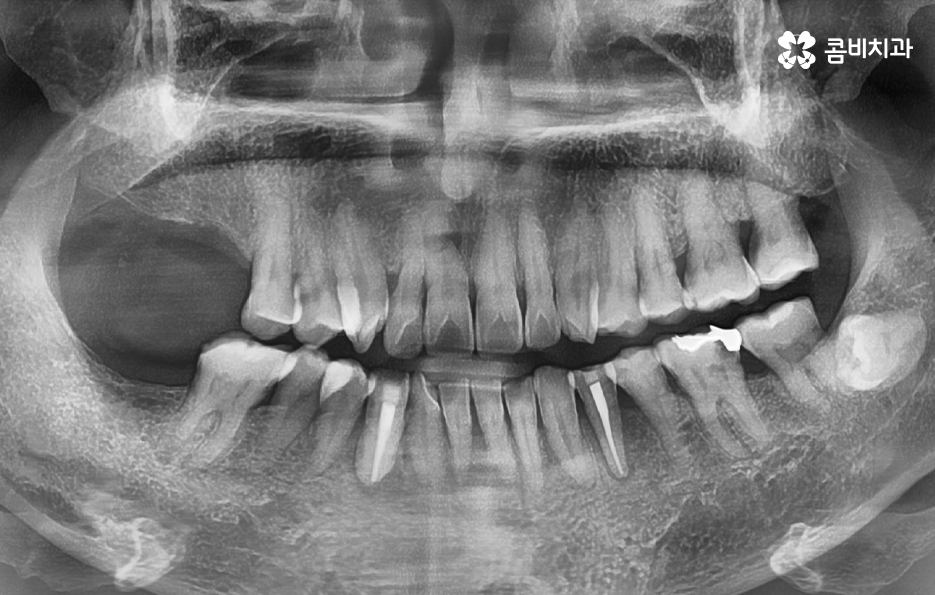

일반적인 임플란트의 치료 과정은 충치나 치주염 등으로 치아를 발치하게 되었을 때 치아 발치 후 잇몸이 아물고 회복되기를 기다리고 있는데요. 잇몸이 충분히 회복된 후에 임플란트를 잇몸 뼈에 식립하는 것을 시작으로 치과 내원과 어금니 임플란트 기간에 대해 대략적으로 알아보면 내원 횟수는 약 45회 정도로 예상되며 평균적으로 34개월 정도면 치료가 마무리 되고 있어요

여기서는 일반적인 치료 과정이라는 점을 전제로 하고 있는데요. 잇몸 뼈 상태가 양호하고 건강한 상태인 경우에 임플란트를 위한 치과 내원 횟수와 기간이 약 45회, 34개월 정도로 예상되는 것이며 잇몸 뼈의 상태가 좋지 않아서 뼈이식이 필요하거나 잇몸 이식술이 필요한 경우에는 치과 내원 횟수와 치료 기간이 더 늘어날 수 있는데요

특히 노인분들의 경우에는 치아를 잃게 되는 주된 원인이 치주염이 심해져서 치아가 흔들리고 발치하게 되는 경우가 많으며 당뇨나 고혈압과 같은 전신질환이 있는 경우도 고려해야 하기 때문에 임플란트의 기본적인 치료 원리는 비슷하지만 각 개인에 따라서 치료기간과 치료 방법이 다소 차이가 날 수 있어요

임플란트의 원리 자체는 어떤 치료에도 비슷하게 적용되지만 치료 계획을 세우다보면 치아를 상실한 원인도 다르고 현재 잇몸 상태부터 전신 건강의 차이가 있기 때문에 세부적인 치료 계획이 달라지면서 임플란트의 치료 방법은 다양하게 적용되고 있는데요